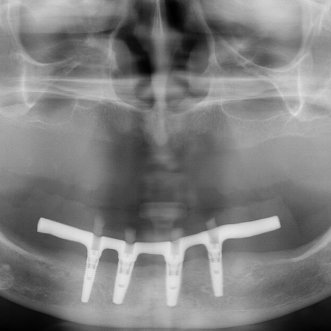

Обратилась с жалобами на отсутствие зубов. Было проведено лечение с установкой 4х имплантатов системы Нобель. Изготовлен условно съемный протез на винтовой фиксации на нижнюю челюсть и полный съемный протез на верхнюю челюсть.